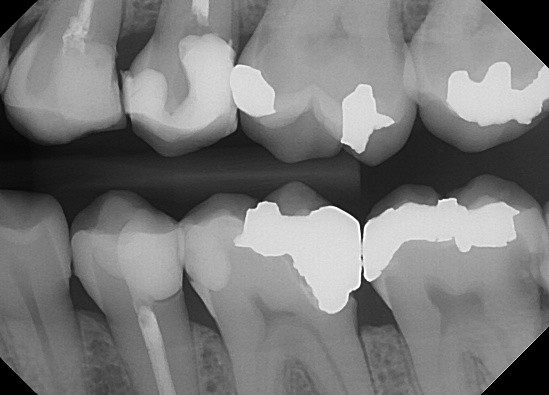

The radiograph shows evidence of

Which of the following is/are seen in the radiograph?